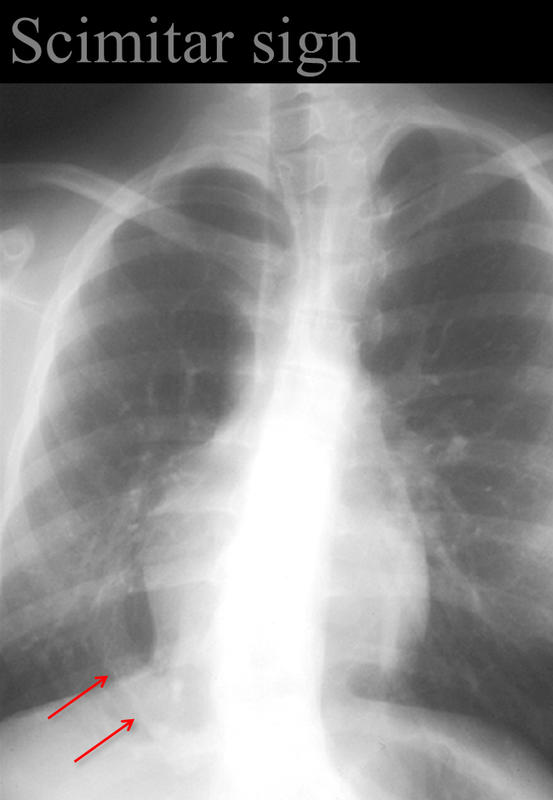

Gallery Signs Scimitar sign Anomalous venus return below the diaphragm (hypoplastic Rt lung/venolobar syndrome)

Scimitar sign

Anomalous venus return below the diaphragm

(hypoplastic Rt lung/venolobar syndrome)